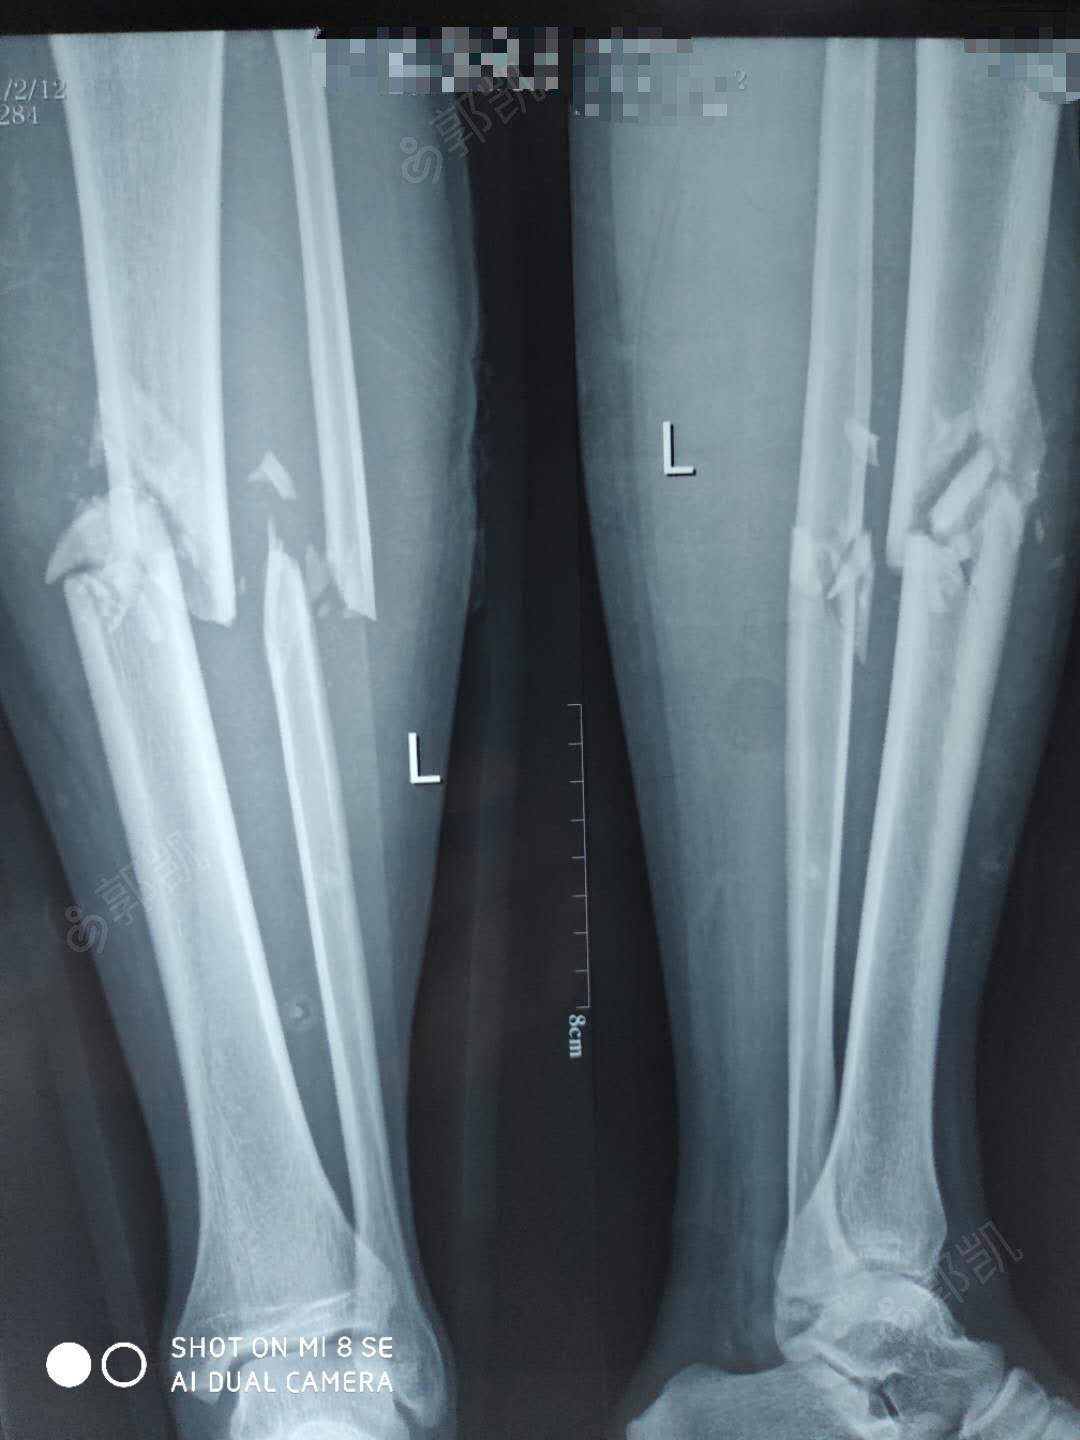

左胫腓骨骨折 2.多处软组织挫伤

图片尺寸1080x1440